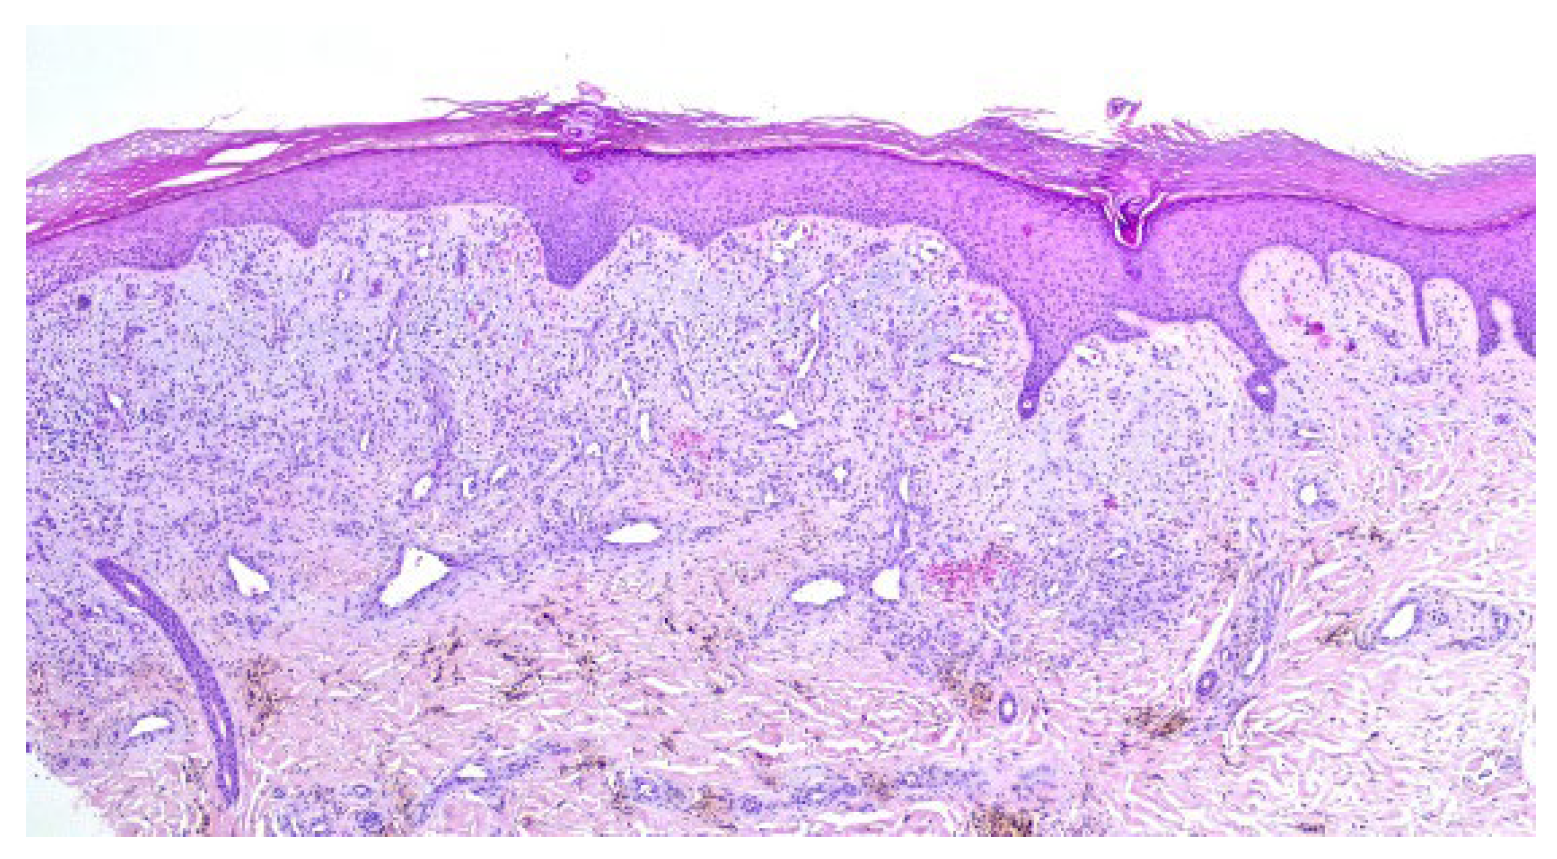

A punch biopsy was performed, and the histopathology disclosed moderate acanthosis, with focal spongiosis and small lymphocyte exocytosis. In the upper dermis, a marked neovascularization, composed of lobules of thick-walled capillaries, was observed in association with erythrocyte extravasation and hemosiderin deposition (Figure 3 and Figure 4). Immunochemistry for HHV-8 was negative (Figure 5). The clinicopathological correlation led to the diagnosis of AAD due to a venous malformation. This case illustrates a possible pathophysiological overlap with the venous malformation contributing to venous insufficiency.

Figure 4. Lobules of thick-walled capillaries and hemosiderin deposition.